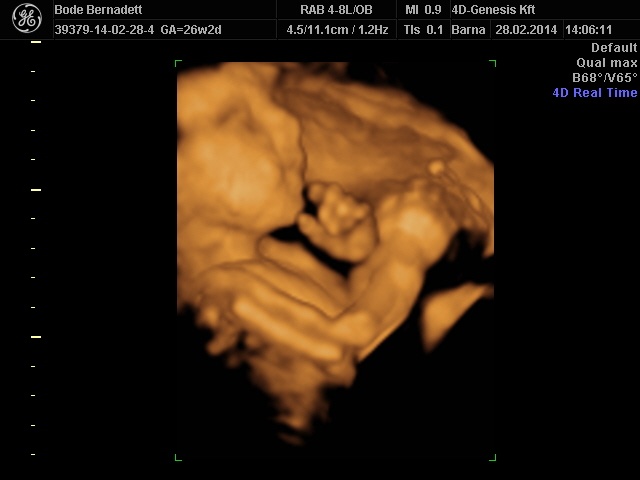

És már biztosan nagyon szépek lesznek a képek, alig várom, hogy feltöltsd, és láthassam. ![]()

Na lányok, én is túl vagyok a cukorterheléses vizsgálatot. Maga cukros löttyel (tettem bele frissen facsart citromlevet) iható volt, azzal nem volt gondom. De utána kint kellett ülnöm a váróban 2 óráig, na az szörnyű volt. Fáztam, melegem volt, szédelegtem, mehetnékem volt, közben majdnem elaludtam. Szóval nem volt jó érzés, de már ez is megvan. Nekünk még 1 hónap van a 4D-ig.